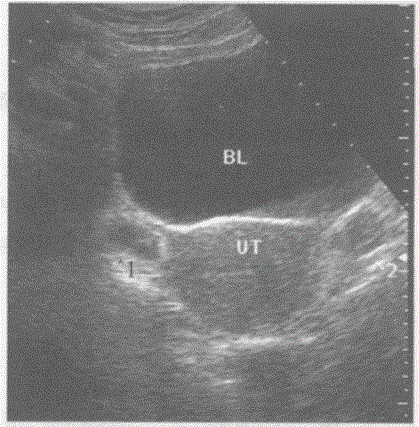

问题 下图是盆腔横切正常超声图像,请回答"^1、^2"所指部位的解剖名称:

选项 A.正常双侧卵巢声像图 B.双侧阔韧带肌瘤 C.正常双侧输卵管声像图 D.盆腔肌肉

答案 A